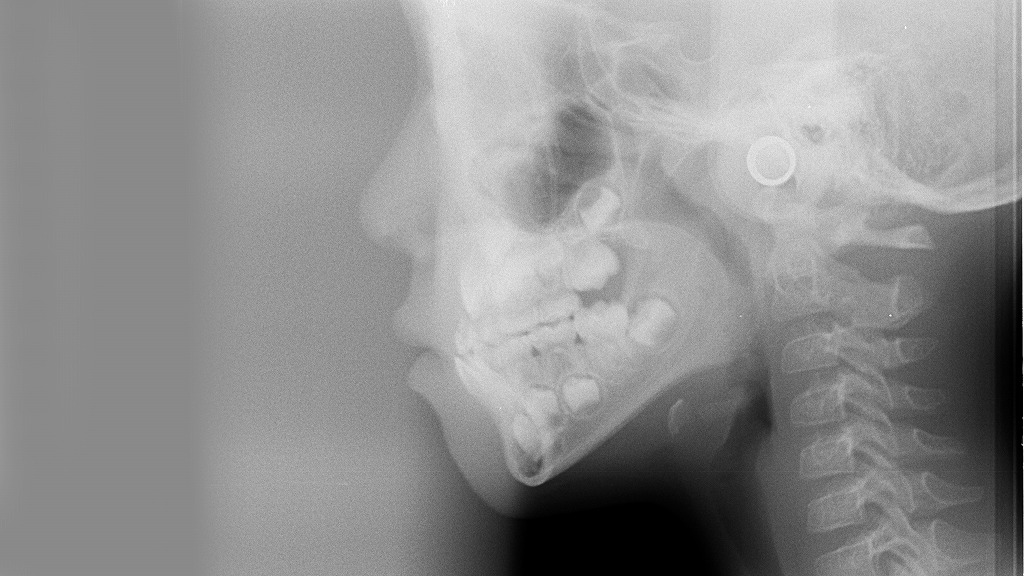

「自分の歯の正中線はズレているのでは?」と不安に感じている方も多いでしょう。正中線のズレはどこまでが許容範囲なのか、そしてどのように診断されるのかを知ることは、必要以上に心配せず、適切な治療を受けるための第一歩になります。

約5mmの正中線のズレがある症例

正中線のズレは奥歯まで影響し、上下の歯はきちっと噛み合っていません。

約6mmの正中線のズレがある症例

向かって右側の犬歯、小臼歯、大臼歯全ての上下の歯が噛み合っていません。

🧠 セファロX線・顔貌写真による正中線の診断方法

正中線のズレを正確に診断するには、肉眼や鏡だけでは不十分です。歯科医院では、以下のような診断ツールを使います。

- セファロ(側面・正面)X線写真:頭蓋骨や歯列の位置関係を科学的に分析

- 顔貌写真(正面・側面):顔全体のバランスを可視化し、正中線のズレを視覚的に評価

- 模型診断:上下の歯型を採取して、咬み合わせを立体的に検証

特にセファロ分析は、顔の中心に対して上顎・下顎・歯列がどの位置にあるのかを数値化できるため、専門的な判断材料として用いられます。